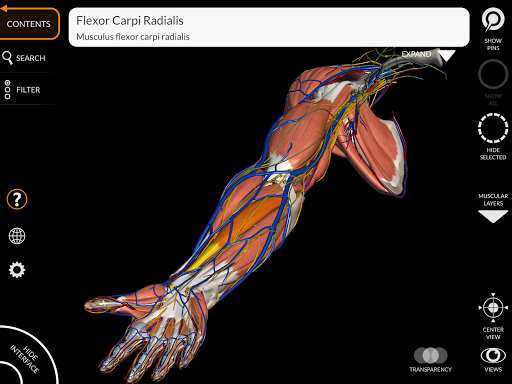

"Anatomy 3D Atlas" cho phép bạn nghiên cứu giải phẫu người theo cách dễ dàng và tương tác.

Thông qua giao diện đơn giản và trực quan, bạn có thể quan sát mọi cấu trúc giải phẫu từ mọi góc độ.

Các mô hình giải phẫu 3D đặc biệt chi tiết và có kết cấu lên đến độ phân giải 4k.

MÔ HÌNH GIẢI PHẪU 3D

• Hệ thống cơ xương

• Hình dung các cơ qua các lớp từ lớp nông đến lớp sâu nhất

• Mô tả các cơ: nguồn gốc, chèn, chi phối thần kinh và hành động